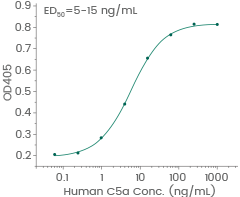

Human C5a protein

Cat#: 10604-HNAE

Induced N-acetyl-β-D-glucosaminidase release from differentiated U937 human histiocytic lymphoma cells. Image Credit: Sino Biological Inc.